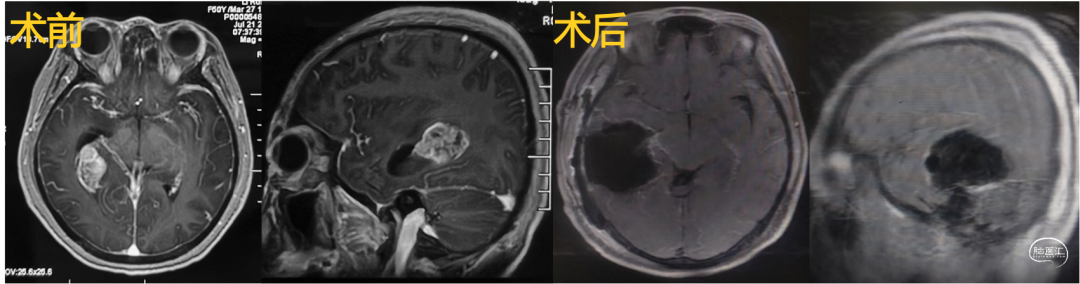

1.基底节-丘脑-颞叶内侧肿瘤切除术